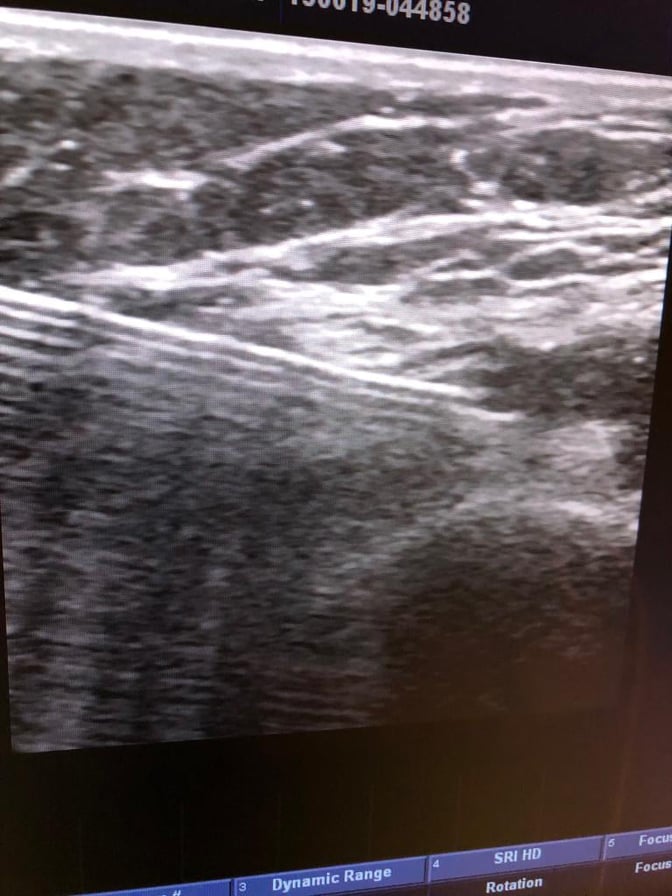

Ağrı Mərkəzinin rəhbəri, alqoloq, artroz xəstəliyinin müalicəsini ən son metodlarla tətbiq edən dr. Zülfüqar Yusifov bildirdi ki,  diz, bud, çanaq, çiyin oynaqdaxili inyeksiyalarda hədəfə düzgün çatmaq üçün ən yaxşı metod prosedurun ultrasəs altında, yəni UZİ ilə icra olunmasıdır. Bu üsul ağrısız, təhlükəsiz, həkim üçün daha uğurlu nəticə verən metoddur. Yalnız bu halda istifadə olunan component oynaq boşluğuna düşür.

Videoda doktorun artrozlu xəstənin diz oynağına USM kontrolu altında oynaq mayesi yeridilməsi təqdim olunur.